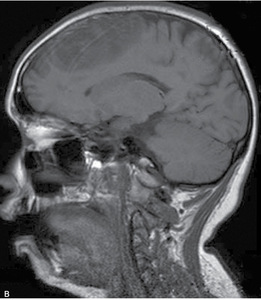

Rutynowa tomografia komputerowa bez środka cieniującego w 20% przypadkach pozwala stwierdzić hiperintensywne skrzepliny w rzucie zatok lub żył mózgowia (dense clot sign) (ryc. 1). W przypadku zakrzepicy żył korowych niekiedy widoczny jest tzw. objaw struny (czyli linijna, hiperintensywna zmiana odpowiadająca zakrzepowi w świetle naczynia żylnego). Pośrednim objawem CVT są cechy obrzęku mózgu (np. spłycenie bruzd, zwężenie układu komorowego, obserwowano w 20-50% przypadków). Charakterystyczna dla udaru żylnego jest lokalizacja ogniska naczyniopochodnego (zarówno niedokrwiennego, jak i krwotocznego) nie odpowiadająca zakresowi unaczynienia tętnic mózgowych, oraz liczne izolowane ogniska położone podkorowo z zaoszczędzeniem kory mózgu.11 Zakrzepica zatoki prostej zwykle upośledza drenaż żylny na dużym odcinku, co skutkuje zmianami zlokalizowanymi w rejonie parasagitalnym (ryc. 2A, B). Zakrzepica żyły zespalającej dolnej (żyła Labbego) prowadzi do zmian w płacie skroniowym. Zakrzepica żył głębokich mózgu powoduje jednostronne lub obustronne zmiany we wzgórzach, jądrach podstawy i torebce wewnętrznej.11W około 30-40% przypadków CVT towarzyszą ogniska krwotoczne. Zgodnie ze stanowiskiem ekspertów American Heart Association (AHA) i American Stroke Association (ASA) w przypadkach krwotoków płatowych o niejasnej etiologii i (lub) lokalizacji nieodpowiadajęcej zakresowi unaczynienia tętniczego, należy brać pod uwagę możliwość CVT.4,11